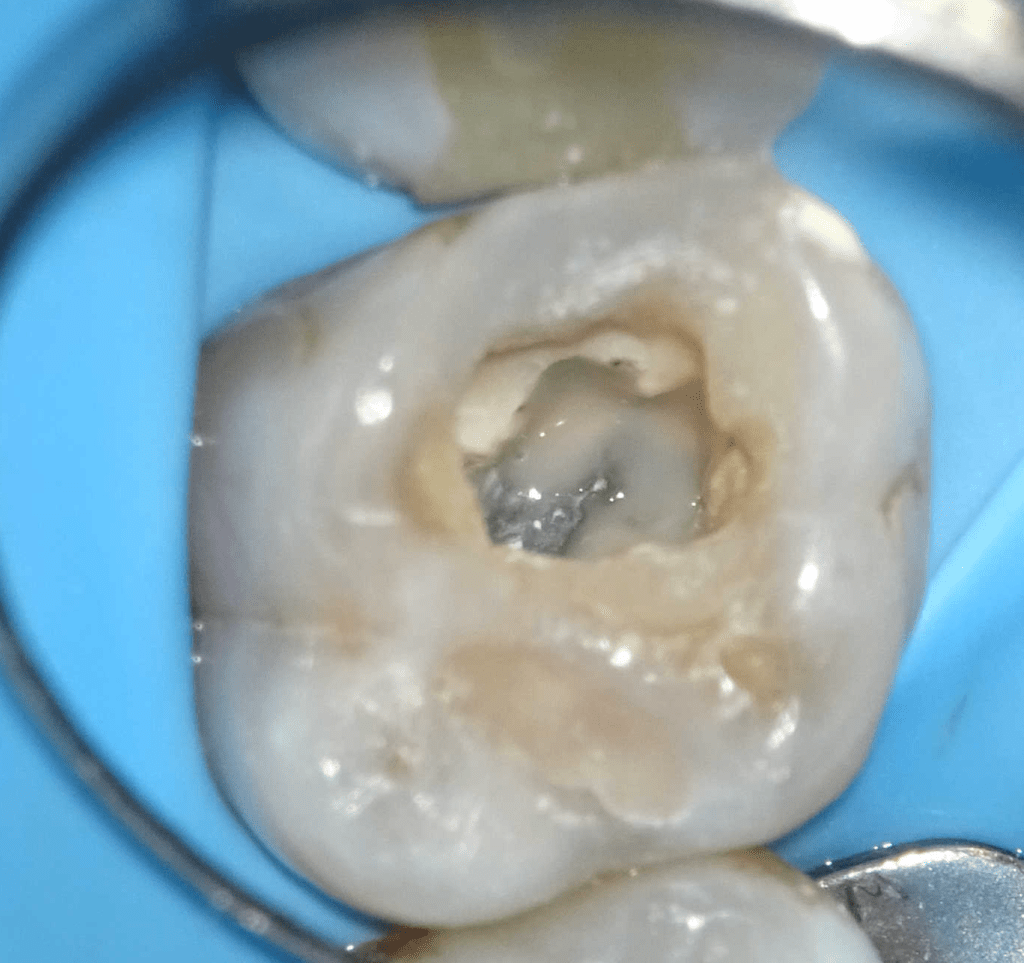

Pulpotomía biodentine + reco preendio